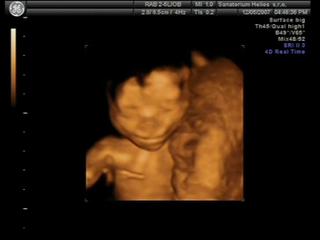

@valmark Já na 3D byla s klukem a to byla paráda, jak tam byl samotnej. Teď s klukama jsem šla taky, ale spíš jen proto, abych měla pro ně stejný fotečky jako pro Karímka.. kluci byli příčně, každej s hlavou na opačný straně, tak mám fotku jednoho s nohou toho druhýho v obličeji..asi prvních 5minut bylo něco poznat, ale pak se tam šmrdolilo pořád nějak moc rukou a nohou najednou, byla to taková změť , že se nic moc nedalo poznat. Ne že bych byla tak moc zklamaná, ale asi bych do toho s dvojčatama znova nešla..Zkusím tu pěknou fotku někde vyhrabat a poslat na ukázku..

Jinak my na tom 3D utz byli a taky bych ho ozelela. U tech dvojcatek nic moc,vsechno se tam mele pres sebe,ze tam neni nic moc poznat. Takze z tech fotek jsme rozeznali maximalne oblicej a zbytek byl takovej maglajs zlute hmoty🙂

@atreides Byla jsem přesně ve 24+0tt. Každýho chlapečka mám jednou vyfocenýho a ani jsme si nemohli z fotek vybírat, prvních 5minut sestřička chytla každýho kluka jednou a pak už nic..jen chumel rukou a nohou ☹

Tak tohle jsou moji chlapečci..na tý druhý fotce je vidět nožička prvního chlapečka, kopal bráchu do obličeje 😀